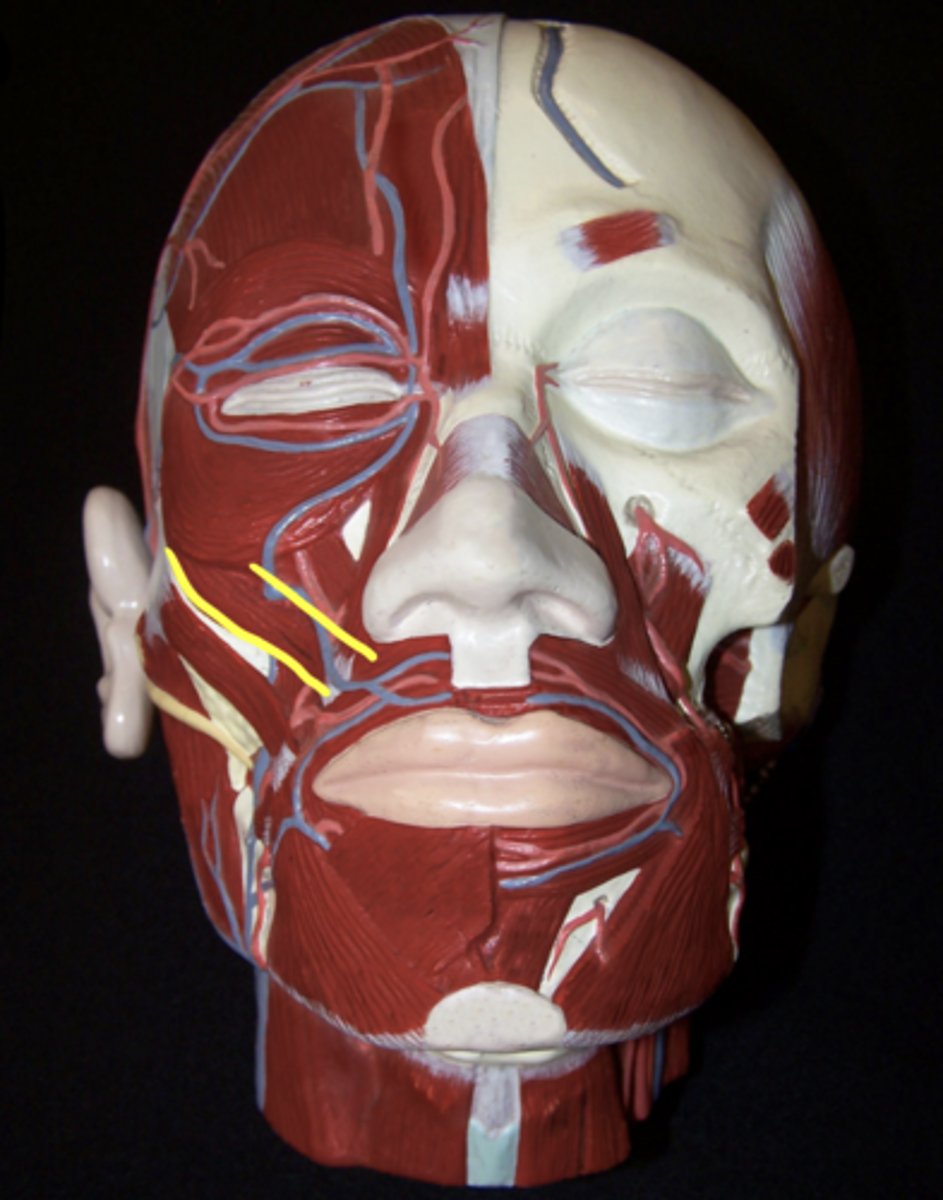

Temporalis

Masseter

Medial Pterygoid

Lateral Pterygoid